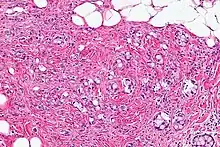

| Micrograph showing a goblet cell carcinoid. H&E stain. | |

Micrograph of a goblet cell carcinoid. H&E stain.

GCCs are diagnosed by pathology. They have a characteristic biphasic appearance which includes (1) goblet cell-like cells, and (2) neuroendocrine-type nuclear chromatin (stippled chromatin).